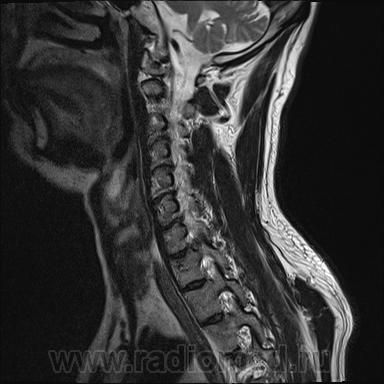

Шейный остеохондроз.Грыжа С7-Th1.Не исключено наличие миелопатии на этом уровне, но боюсь ошибиться-изображения мелковаты ,идаже кажется, что есть повышение МРС от спинного мозга по Т1( скорее всего-артефакты?).

Левосторонняя парамедианная с компрессией корешка.

а это не перидурит??? смотрели месяц назад (в начале заболевания) было меньше.

Посмотрите на STIRе. Если жидкости нет, то простая грыжа. На этих сканах вообще-то жидкости не видно. За месяц грыжа могла и подрасти, смотря как лечили.

По-моему, только грыжа.